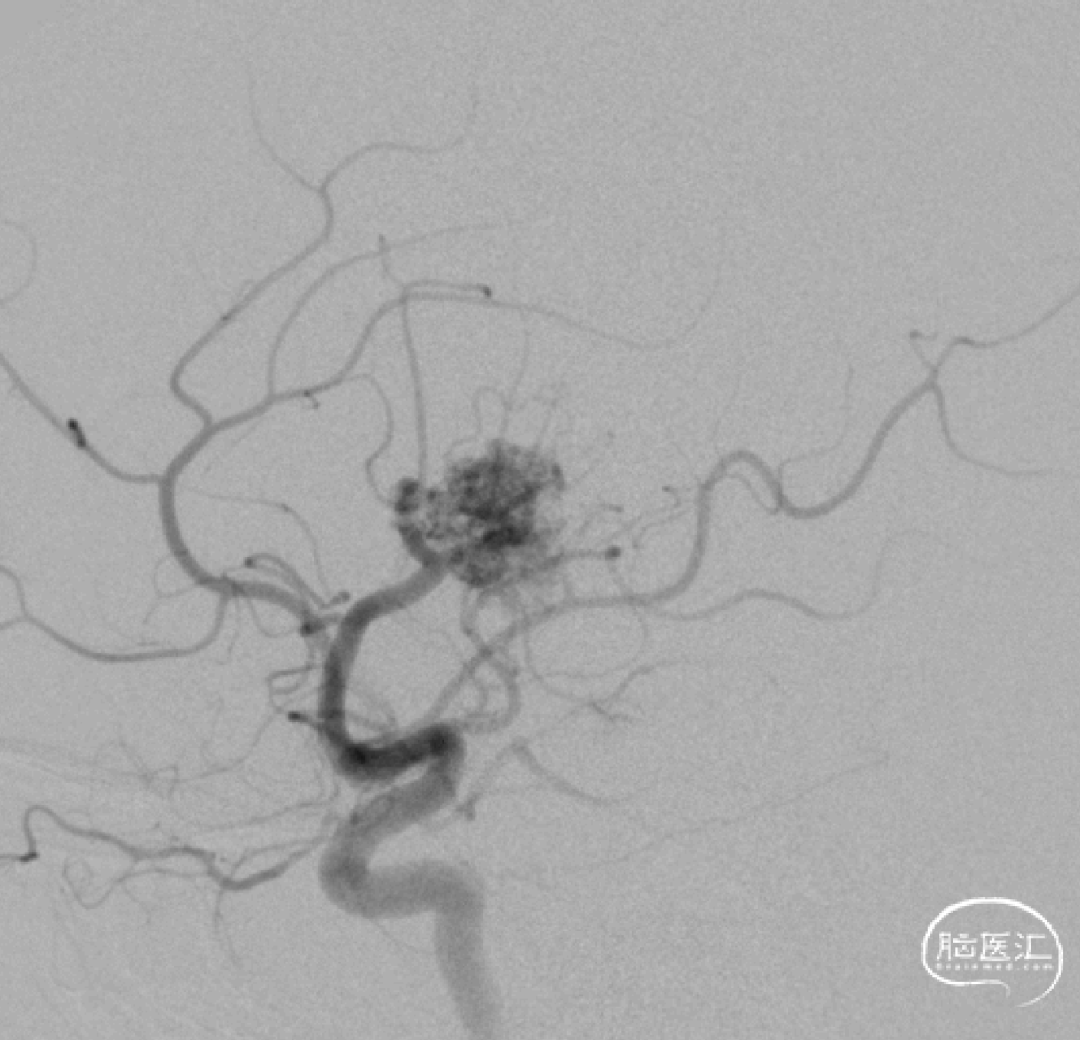

术前DSA

术中动脉造影

动静脉联合3d显示引流静脉与矢状窦关系;中天21微导管塑形(半圆)支撑下FATHOM-14导丝超选成功,考虑enchlon10长度不够,截断中管;FATHOM-14 3m交换enchelon10,但阻力大未能到位,中间管也未能到引流静脉入口;头羊作用下apollo3cm超选到位。

球囊保护静脉入路栓塞:注射onyx34约1ml,onyx18约1.5ml,总时长20min。

术后即刻造影畸形血管团不显影